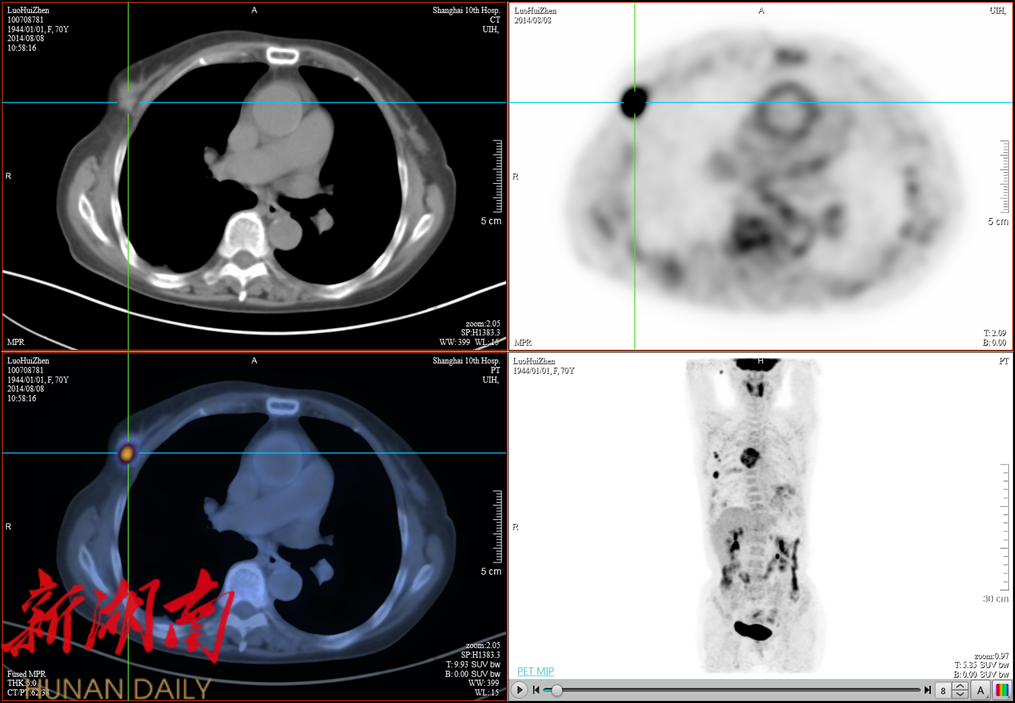

这款PET-CT设备配备了280毫米的超大轴向扫描视野,能够显著缩短扫描时间,提高检查效率。该设备采用的全新数字光导探测器相较于老式PET-CT的普通光导探测器或其他晶体探测器,在分辨率和灵敏度上实现了质的飞跃。凭借1.4毫米的超高清分辨率,该设备能够精准捕捉更微小的病灶,为肿瘤患者的早期发现和治疗提供了强有力的支持。

△超高清分辨率图像,精准显示微小病变

△1.4mm细微结构清晰显像,类MR至真完美图像

PET-CT作为一种高端医学影像技术,目前广泛应用于高端体检以及肿瘤、心脑血管等疾病的诊断和复查中。利用PET-CT进行全身体检,可以早期发现全身微小的各种病变,尤其是那些其他设备难以发现的早期恶性肿瘤病变。这一目前最先进的诊断和体检设备的引入,无疑为南华医院在肿瘤的早期诊断和治疗方面增添了新的利器,也为广大患者带来了福音。